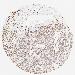

CANCER BREAST CANCER Show tissue menu

BRCA TCGA BRCA VALIDATION PROTEIN EXPRESSION